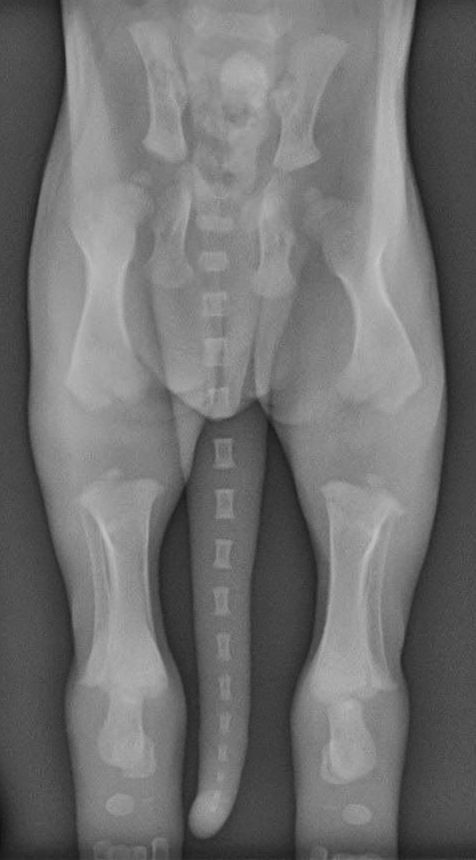

Y para muestra, un botón. En esta tabla te ponemos los tiempos de cierre de las placas de crecimiento de un cachorro:

| HUESO | CIERRE PLACA DE CRECIMIENTO |

|---|---|

| Húmero (a la altura de la escápula) | 10-12 meses |

| Radio (a la altura del codo) | 9-11 meses |

| Huesos de los dedos | 6-7 meses |

| Huesos de la pelvis | 5-6 meses |

| Fémur (a la altura de la cadera) | 9-11 meses |

| Tibia (a la altura de la rodilla) | 10-14 meses |

Y aquí te ilustramos de lo que estamos hablando con varias radiografías de cachorros en las que puedes ver perfectamente que los huesos parecen «flotar» en el espacio: